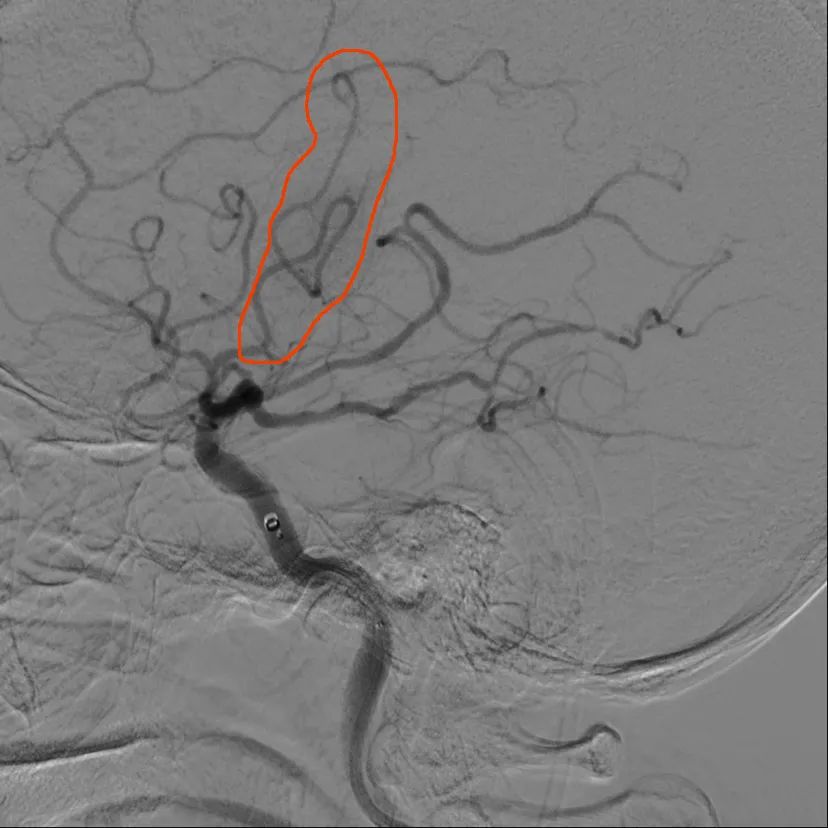

16 时 55 分,梅爷爷被送入介入室,在脑卒中绿色通道救治团队快速且充分的准备后,17 时 10 分,神经疾病科史树贵教授、翟红教授、卢龙医师紧急为梅爷爷行脑血管造影+脑动脉支架取栓术。

17 时 56 分,堵在梅爷爷右侧大脑动脉的血栓被取出,手术顺利完成。

上图为取栓前,中图为取栓后,下图为取出血栓